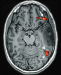

Functional Magnetic Resonance Imaging (fMRI) in Brain Tumour Patients European Association of NeuroOncology Magazine 2012; 2 (3): 123-128 PDF Summary Figures Keywords: brain mapping, brain neoplasms, functional, glioma, magnetic resonance imaging, motor cortex Functional magnetic resonance imaging (fMRI) is increasingly used in the work-up of brain tumour patients preoperatively to assess the relationship between the functionally eloquent cortex and brain pathology. In cases of presumed tumour localisation in or near eloquent brain areas, such as the motor cortex or language areas, fMRI may be advantageous to guide the neurosurgical approach, shorten surgery duration, and obtain prognostic information prior to surgery. For the assessment of the primary motor cortex a good correlation between fMRI and intraoperative electrocortical mapping (ECM) has been reported, with sensitivities and specificities ranging from 88–100 %. For the localisation of language representation areas validation results are controversial with sensitivities from 22–100 % and specificities from 0–100 %, rendering fMRI less suitable as the sole technique for language cortex localisation. For the assessment of hemispheric language lateralisation, however, > 90 % agreement between fMRI and the invasive Wada test has led to fMRI now mostly having replaced the Wada test for this indication. There are several limitations of fMRI including issues that are inherent to the technique such as spatial and geometric uncertainty, tumour effects on the fMRI signal, interand intra-individual variability, lack of discrimination between essential and modulating brain regions, and lack of information on the underlying white matter. Such shortcomings need to explicitly be taken into account in every patient. The careful use of fMRI is justified to aid neurosurgical planning but intraoperative ECM remains the gold standard for localising the eloquent brain cortex. |